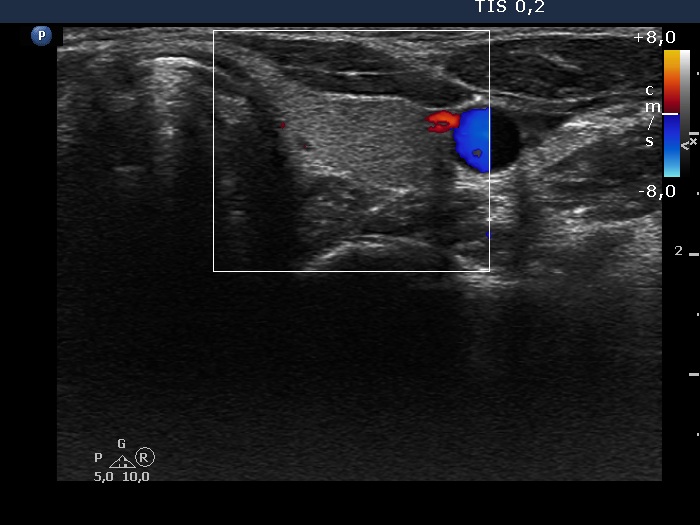

Right lobe, longitudinal scan

Left lobe, trasnverse scan, color Doppler mode. There is no vascularization on Doppler mode.